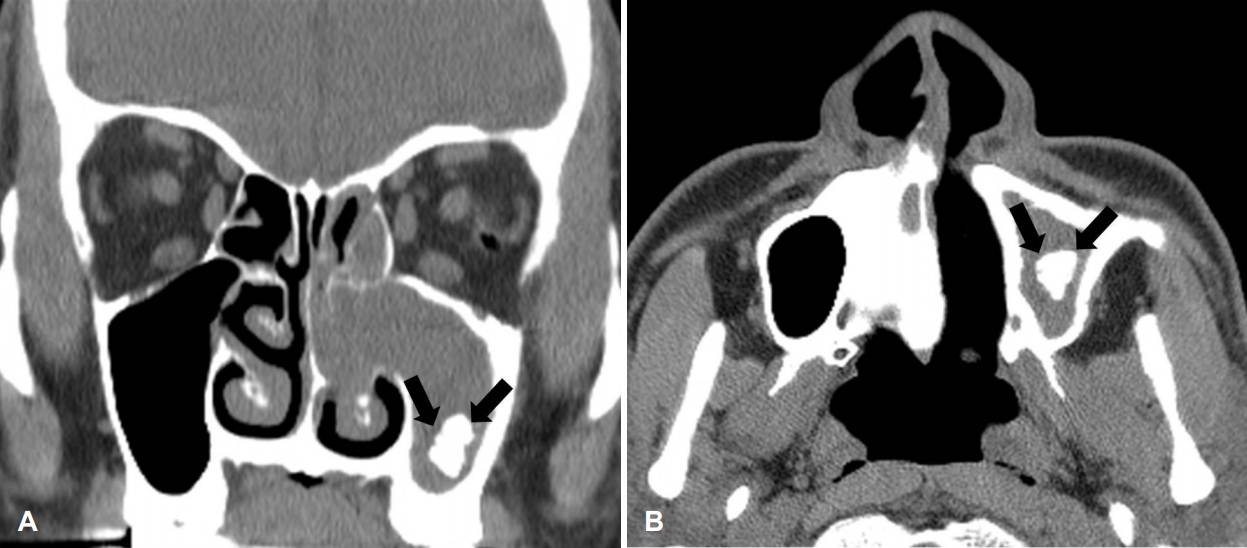

A 67-year-old man was admitted to our clinic with rhinorrhea and nasal obstruction of the left nasal cavity that had developed approximately 1 month ago. He did not have symptoms such as facial pain, swelling, bleeding, or foul odor. There was no underlying disease except allergic rhinitis in his past history. Although he underwent treatment of dental caries in the right lower first molar 6 months ago, there was no history of dental problem in the upper molar area. Endoscopic examination showed a nasal polyp and mucopurulent discharge in the left nasal cavity (Fig. 1). CT of the paranasal sinuses showed soft tissue density and calcification in the left maxillary sinus, which is consistent with signs of a fungal ball (Fig. 2). There was no feature that was suspicious of malignancy, such as destruction and invasion of the surrounding structures. Endoscopic sinus surgery was planned under local anesthesia for histopathologic diagnosis and treatment with the suspicion of a fungal ball.